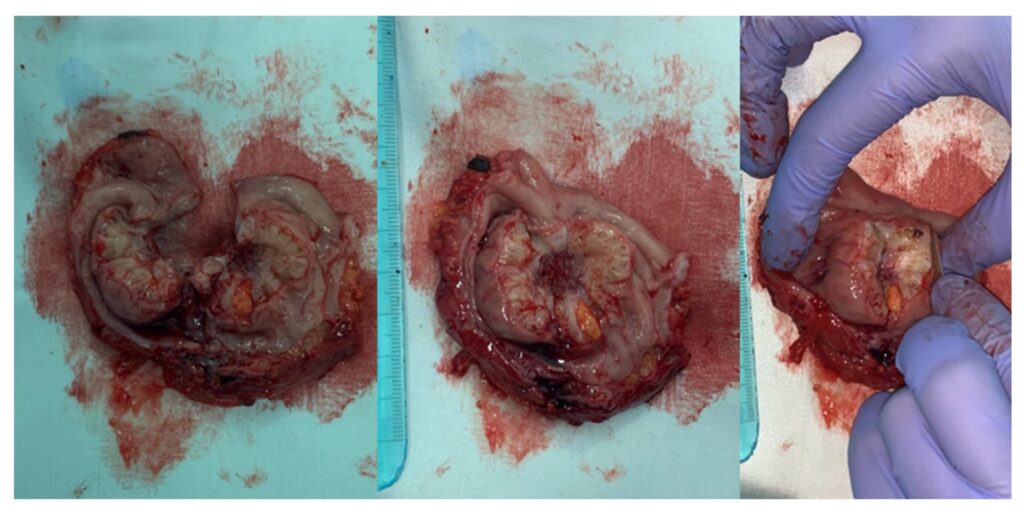

Denne forhøjede risiko er hovedårsagen til, at læger ofte anbefaler kirurgisk fjernelse af alt synligt endometriosevæv, inklusive en eventuel hysterektomi (fjernelse af livmoder) med bilateral salpingo-ooforektomi (fjernelse af æggeledere og æggestokke), for at sikre, at der ikke er skjulte kræftceller og for at fjerne kilden til potentielle fremtidige problemer.